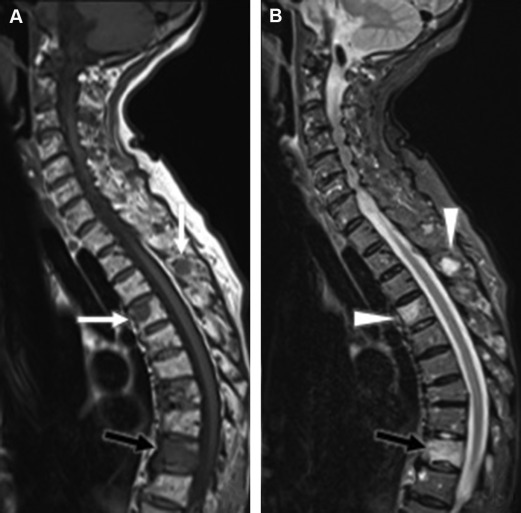

spinal dural AVF

present with gradual but progressive pain, leg weakness/numbness, bladder/bowel changes

flow voids on T2

can see intramedullary hyperintensity due to edema, often involving conus

confirmed with DSA